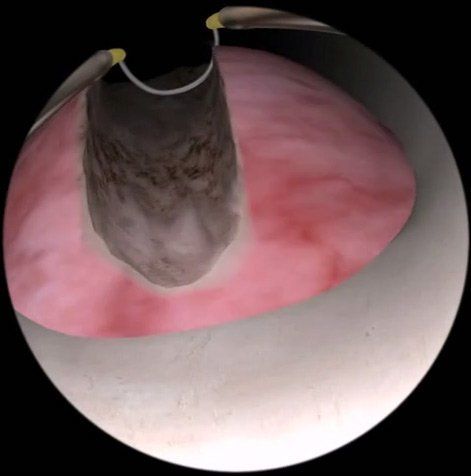

Traitement chirurgical